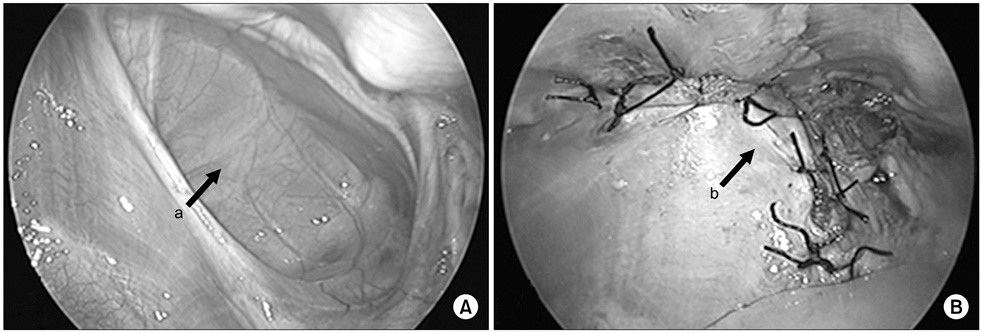

Congenital diaphragm hernia. (A) There was hernia sac on right diaphragmatic defect. (B) Hernia sac was excised and primary repair was performed. Arrows: a, hernia sac; b, primary closure.

Fig. 6 Congenital diaphragm hernia. (A) There was hernia sac on right diaphragmatic defect. (B) Hernia sac was excised and primary repair was performed. Arrows: a, hernia sac; b, primary closure.